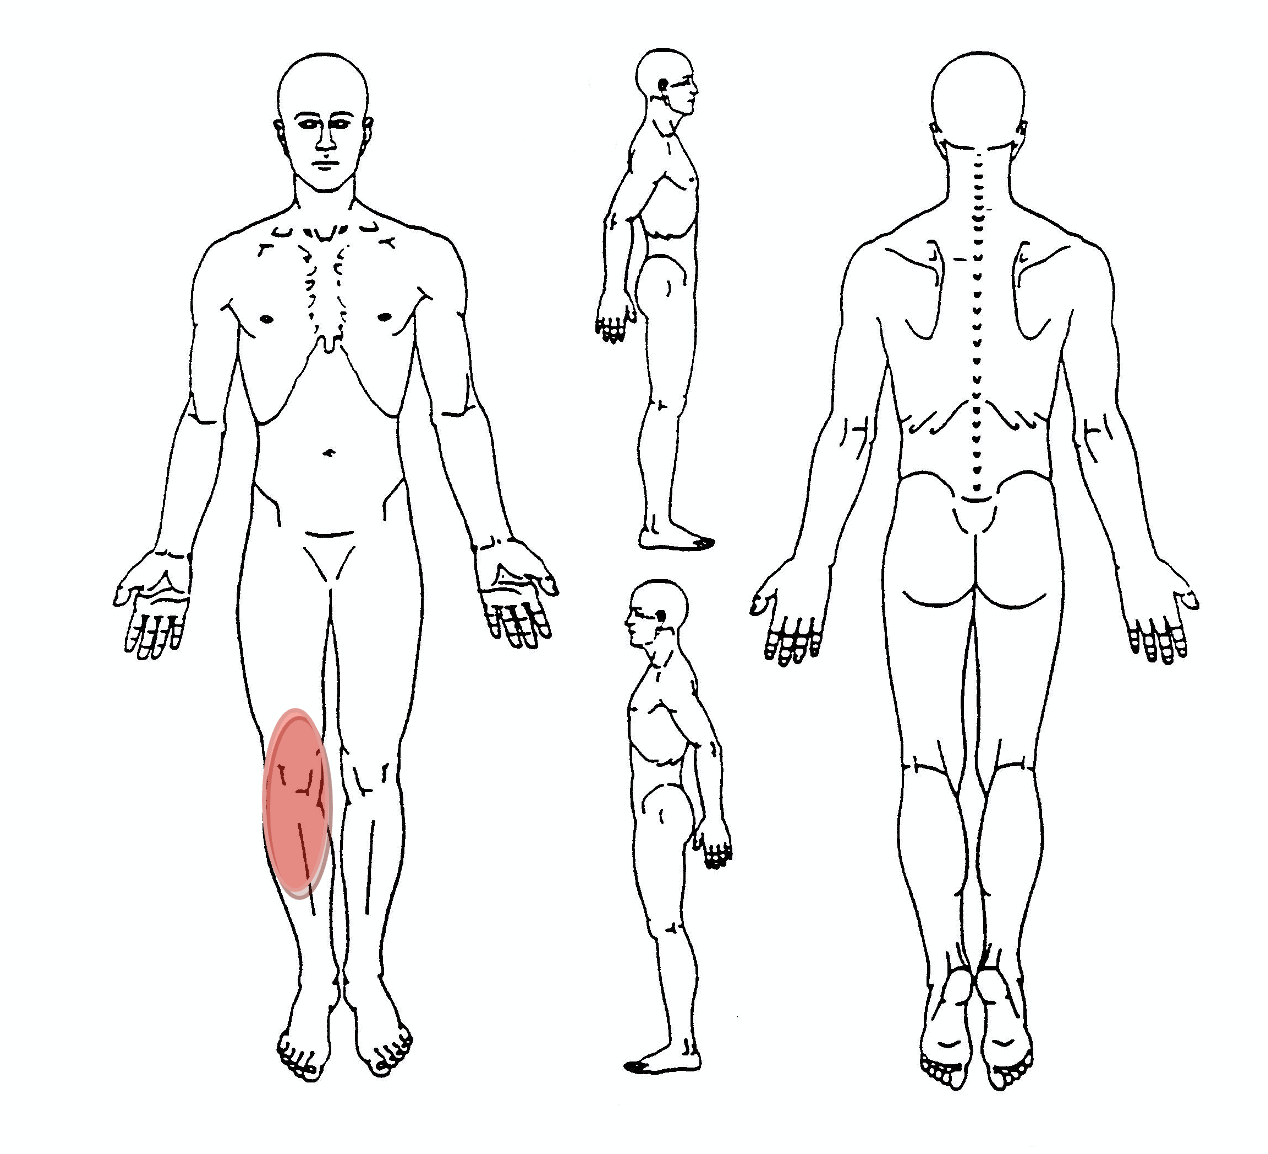

Patellofemorales Schmerzsyndrom

Symptom Diagram

- Schmerzen hinter oder um die Kniescheibe, die in das gesamte Knie ausstrahlen